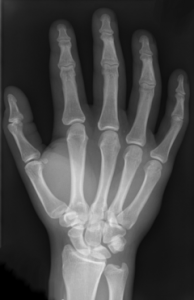

How to treat carpel tunnel syndrome